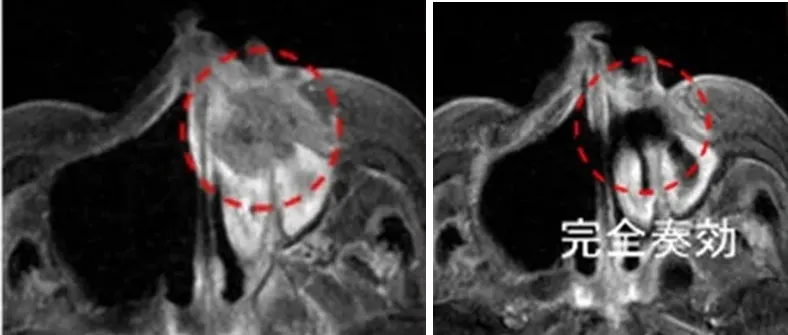

一位80多岁女性,牙龈癌放化疗后复发,BNCT治疗1个月后,MRI显示肿瘤达到完全缓解。